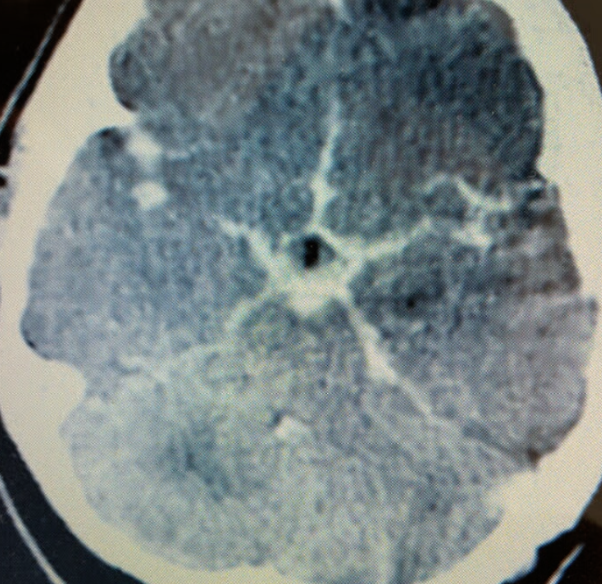

Case 2

What’s ur finding ?

What’s ur finding ?

Star sign!!

Diagnosis?

Subarachnoid hemorrhage